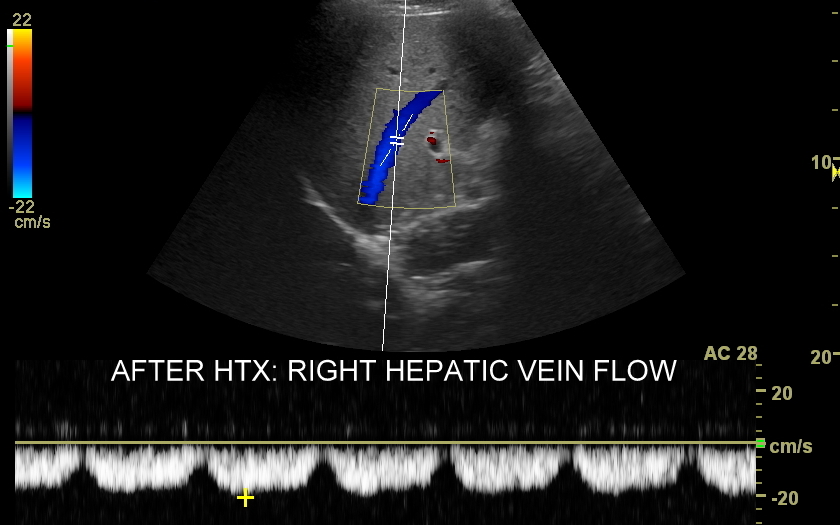

USG przeszczepionej wątroby

Ocena USG wątroby po przeszczepie, w tym Doppler przepływy wątrobowe, wykonywana jest zarówno w bezpośrednim szpitalnym okresie po zabiegu transplantacji, jak i w trakcie regularnej oceny ambulatoryjnej. W ramach badania sprawdzane są cechy ewentualnego odrzucania przeszczepu lub jego zapalenia, prawidłowość unaczynienia wątroby, szczelność połączeń tętniczych, żylnych oraz dróg żółciowych, a także ewentualne oznaki zwężenia lub niedrożności tychże połączeń. Interdyscyplinarna Pracownia USG prowadzona od 2011 r. przez dr Tomasza Szczepańskiego, pierwotnie w Opiece Medycznej Golden Care, jest jedną z niewielu instytucji we Wrocławiu i na Dolnym Śląsku wykonujących ocenę pacjentów po przeszczepach wątroby.